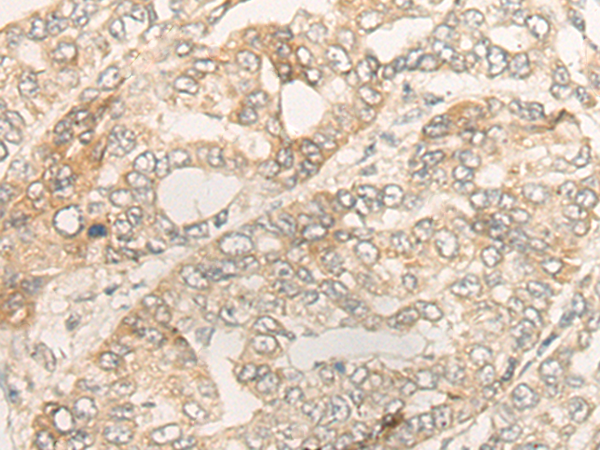

IHC positive control: |

Human liver cancer; |

IHC Recommend dilution: |

30-150 |